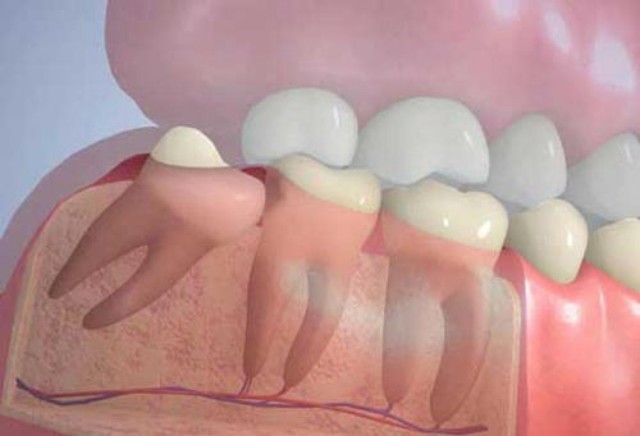

Внешне зуб мудрости практически ничем не отличается от остальных моляров. Он имеет такой же размер и форму, но определенные отличия все же имеются. Восьмерки почти всегда располагаются под небольшим наклоном, что объясняется узостью челюстной дуги и отсутствием места для нормального роста.

Главным отличием зубов мудрости от премоляров и моляров является сложная корневая система. Корни восьмерок обычно больше и длиннее, чем у остальных зубов, и всегда растут под наклоном, часто переплетаясь между собой.

Проблемы с «восьмерками» начинаются еще тогда, когда они не успели вырасти: на этапе их прорезывания. Любое отклонение зуба от вертикальной оси является патологией, которая называется дистопией. В зависимости от направления, в котором отклоняется зуб мудрости, выделяют несколько ее типов:

- Медиальный наклон. Моляр своей верхушкой направлен на впередистоящую семерку. Постоянное давление зубов друг на друга приводит к повреждению эмали, что повышает вероятность развития кариеса с последующим разрушением коронок.

- Дистальный наклон. При этой патологии мудрый зуб расположен с наклоном назад, что частенько сопровождается нарушением прикуса – затрудняется закрытие рта, отмечается хронический болевой синдром.

- Щечный наклон. Восьмерка наклоняется или полностью смещается в сторону щеки.

- Языковой наклон. Неправильное расположение зуба заключается в смещении в сторону языка.

так растут зубы мудрости при дистопии